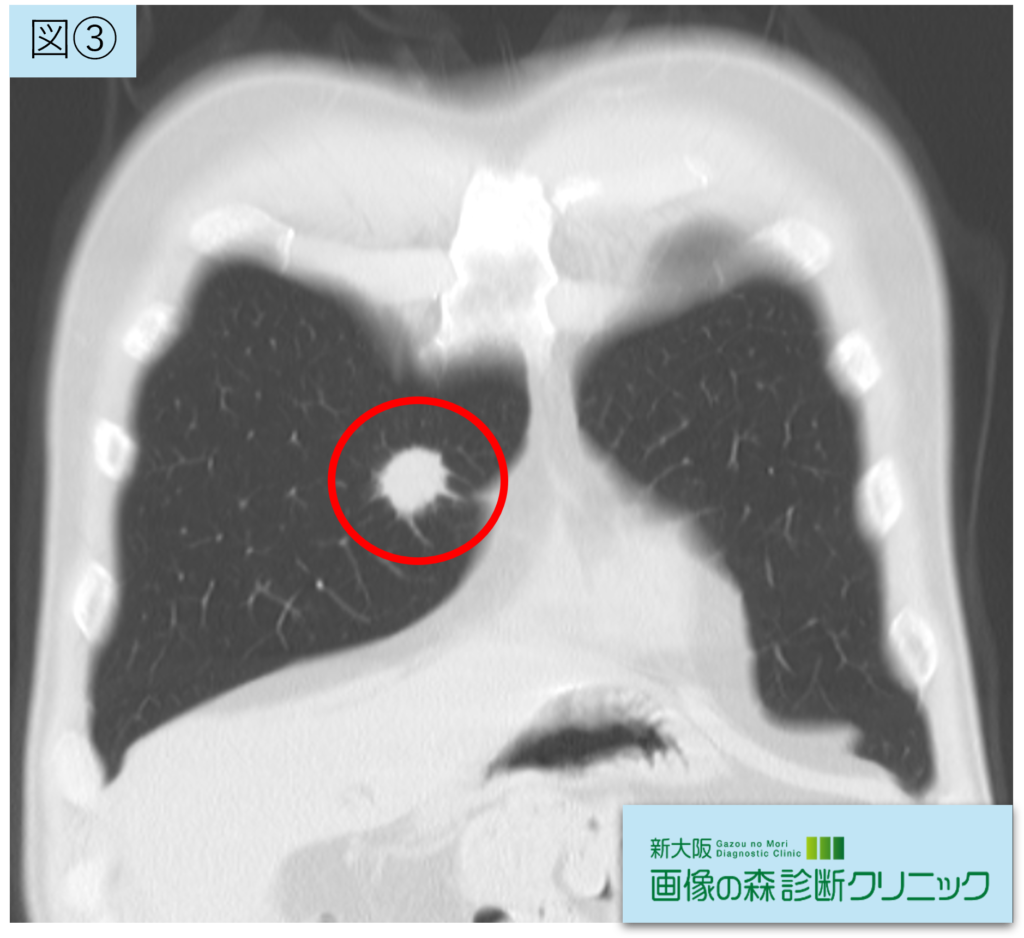

腫瘍画像(冠状断像)

図②③④:腫瘍画像(赤〇が腫瘍部位です)

右肺中葉に21.5mmの腫瘍性陰影を認めます。辺縁不整(スピクラ)の充実性腫瘤を認め、悪性を疑う所見です。